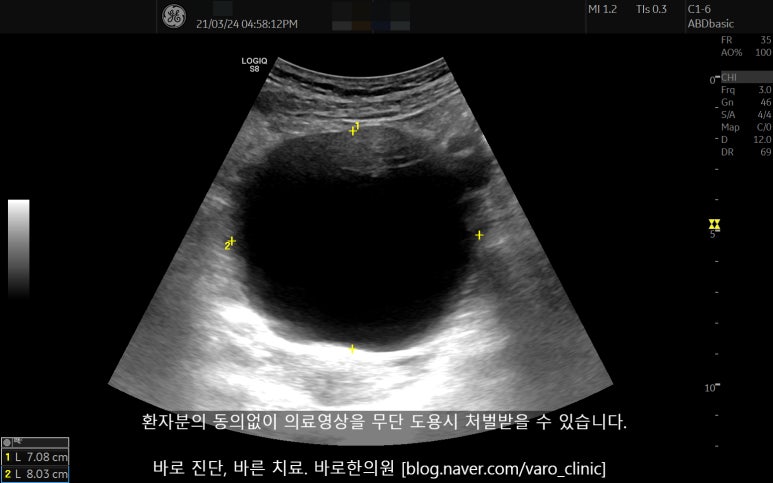

협력 병원에서 골반 초음파 검사상 직경 8cm에 달하는 난소 낭종을 발견했습니다. 주변 장기를 압박하면서 일부 혈관이 꼬여있는 상태였습니다.

거대낭종의 염전은 종양 괴사, 파열, 출혈, 유착 등으로 이어질 수 있는 응급 상황이다보니 곧바로 복강경 수술을 하였고, 조직검사상 양성으로 판정되었습니다.

난소 낭종 환자분 초음파 영상

위 영상은 환자분의 개인정보활용동의를 얻고 올린 의료영상으로무단도용시 법적 책임을 질 수 있습니다.